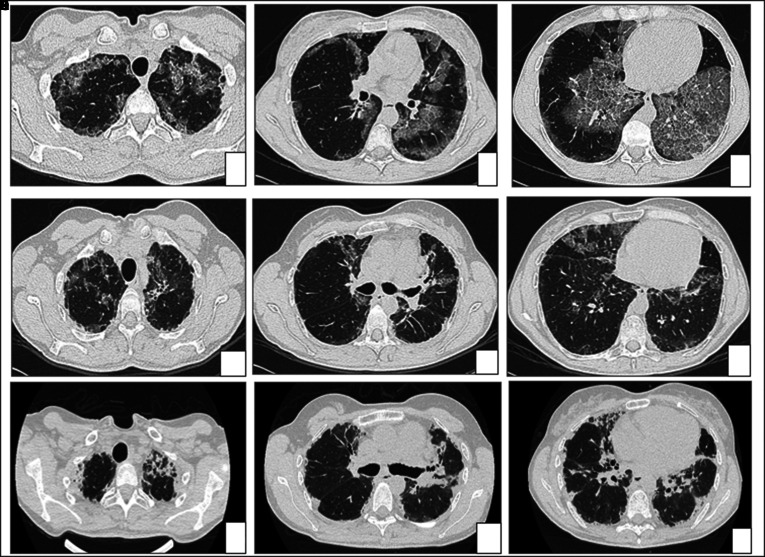

Background: Pulmonary alveolar proteinosis (PAP) has an unpredictable clinical course. Although usually benign, an association with pulmonary fibrosis is described in literature, with troubling therapeutic and prognostic implications.

Clinical case: We report the case of a patient affected by autoimmune PAP who developed pleuro-parenchymal fibroelastosis (PPFE) after 6 years of disease and underwent bilateral lung transplantation due to end stage respiratory failure.

Conclusion: Punctual descriptions of pulmonary fibrosis in PAP are still lacking and no predictors of fibrotic evolution of PAP are known. It is necessary to ensure a strict follow up in order to promptly recognize signs of fibrotic evolution and early refer patients with evolutive disease to lung transplant center. Moreover, an extended genetic analysis by targeted next-generation sequencing could provide high-resolution information that may allow the identification of susceptible patients in a pre-fibrotic stage of disease.